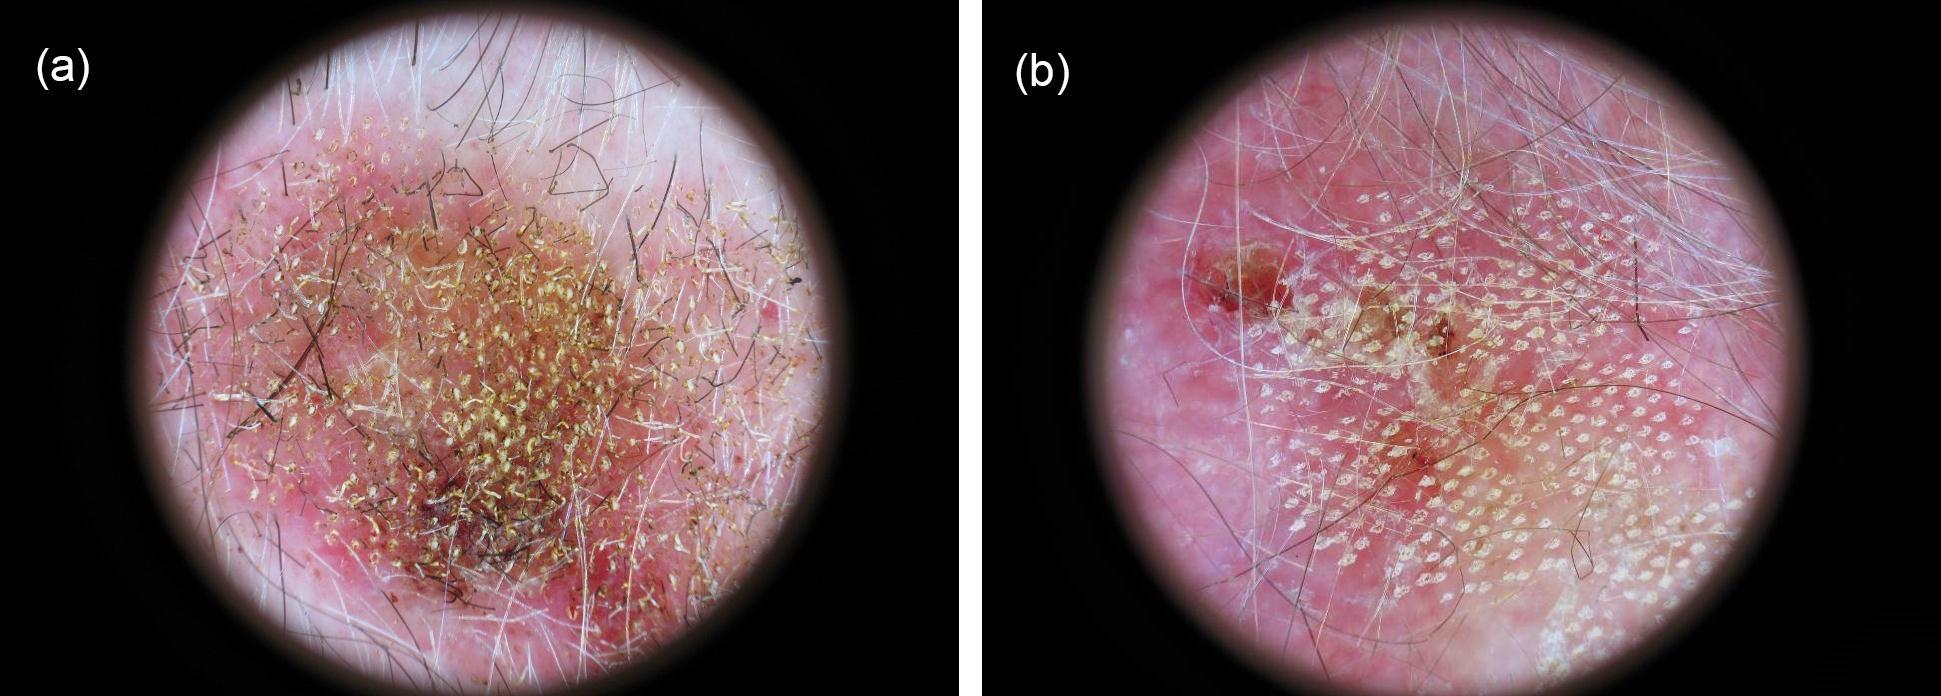

Skin microporation was performed using the fractionated erbium:YAG laser device. The laser generated pulses are in the mid infrared spectrum (wavelength 3µm) with an 1mJ energy at 250 Hz, which translates to 0.25 W average power. Typically, 300 pores/cm2 per shot were set. AK and BCC lesions were microporated with 1-3 overlapping shots at a pulse rate of 3-10 (Figure 1a and b). Next IQM was applied to the micropores by the investigator.

Figure 1.Dermoscopic pictures of two microporated and imiquimod treated lesions: a) Arm 4 basal cell carcinoma showing an initial erythema at day 2. Microporation was performed with 1 shot at 10 pulses. b) Arm 2 actinic keratosis showing erythema, crusting and erosions at day 11. Microporation was performed with 2 shots at 3 pulses.